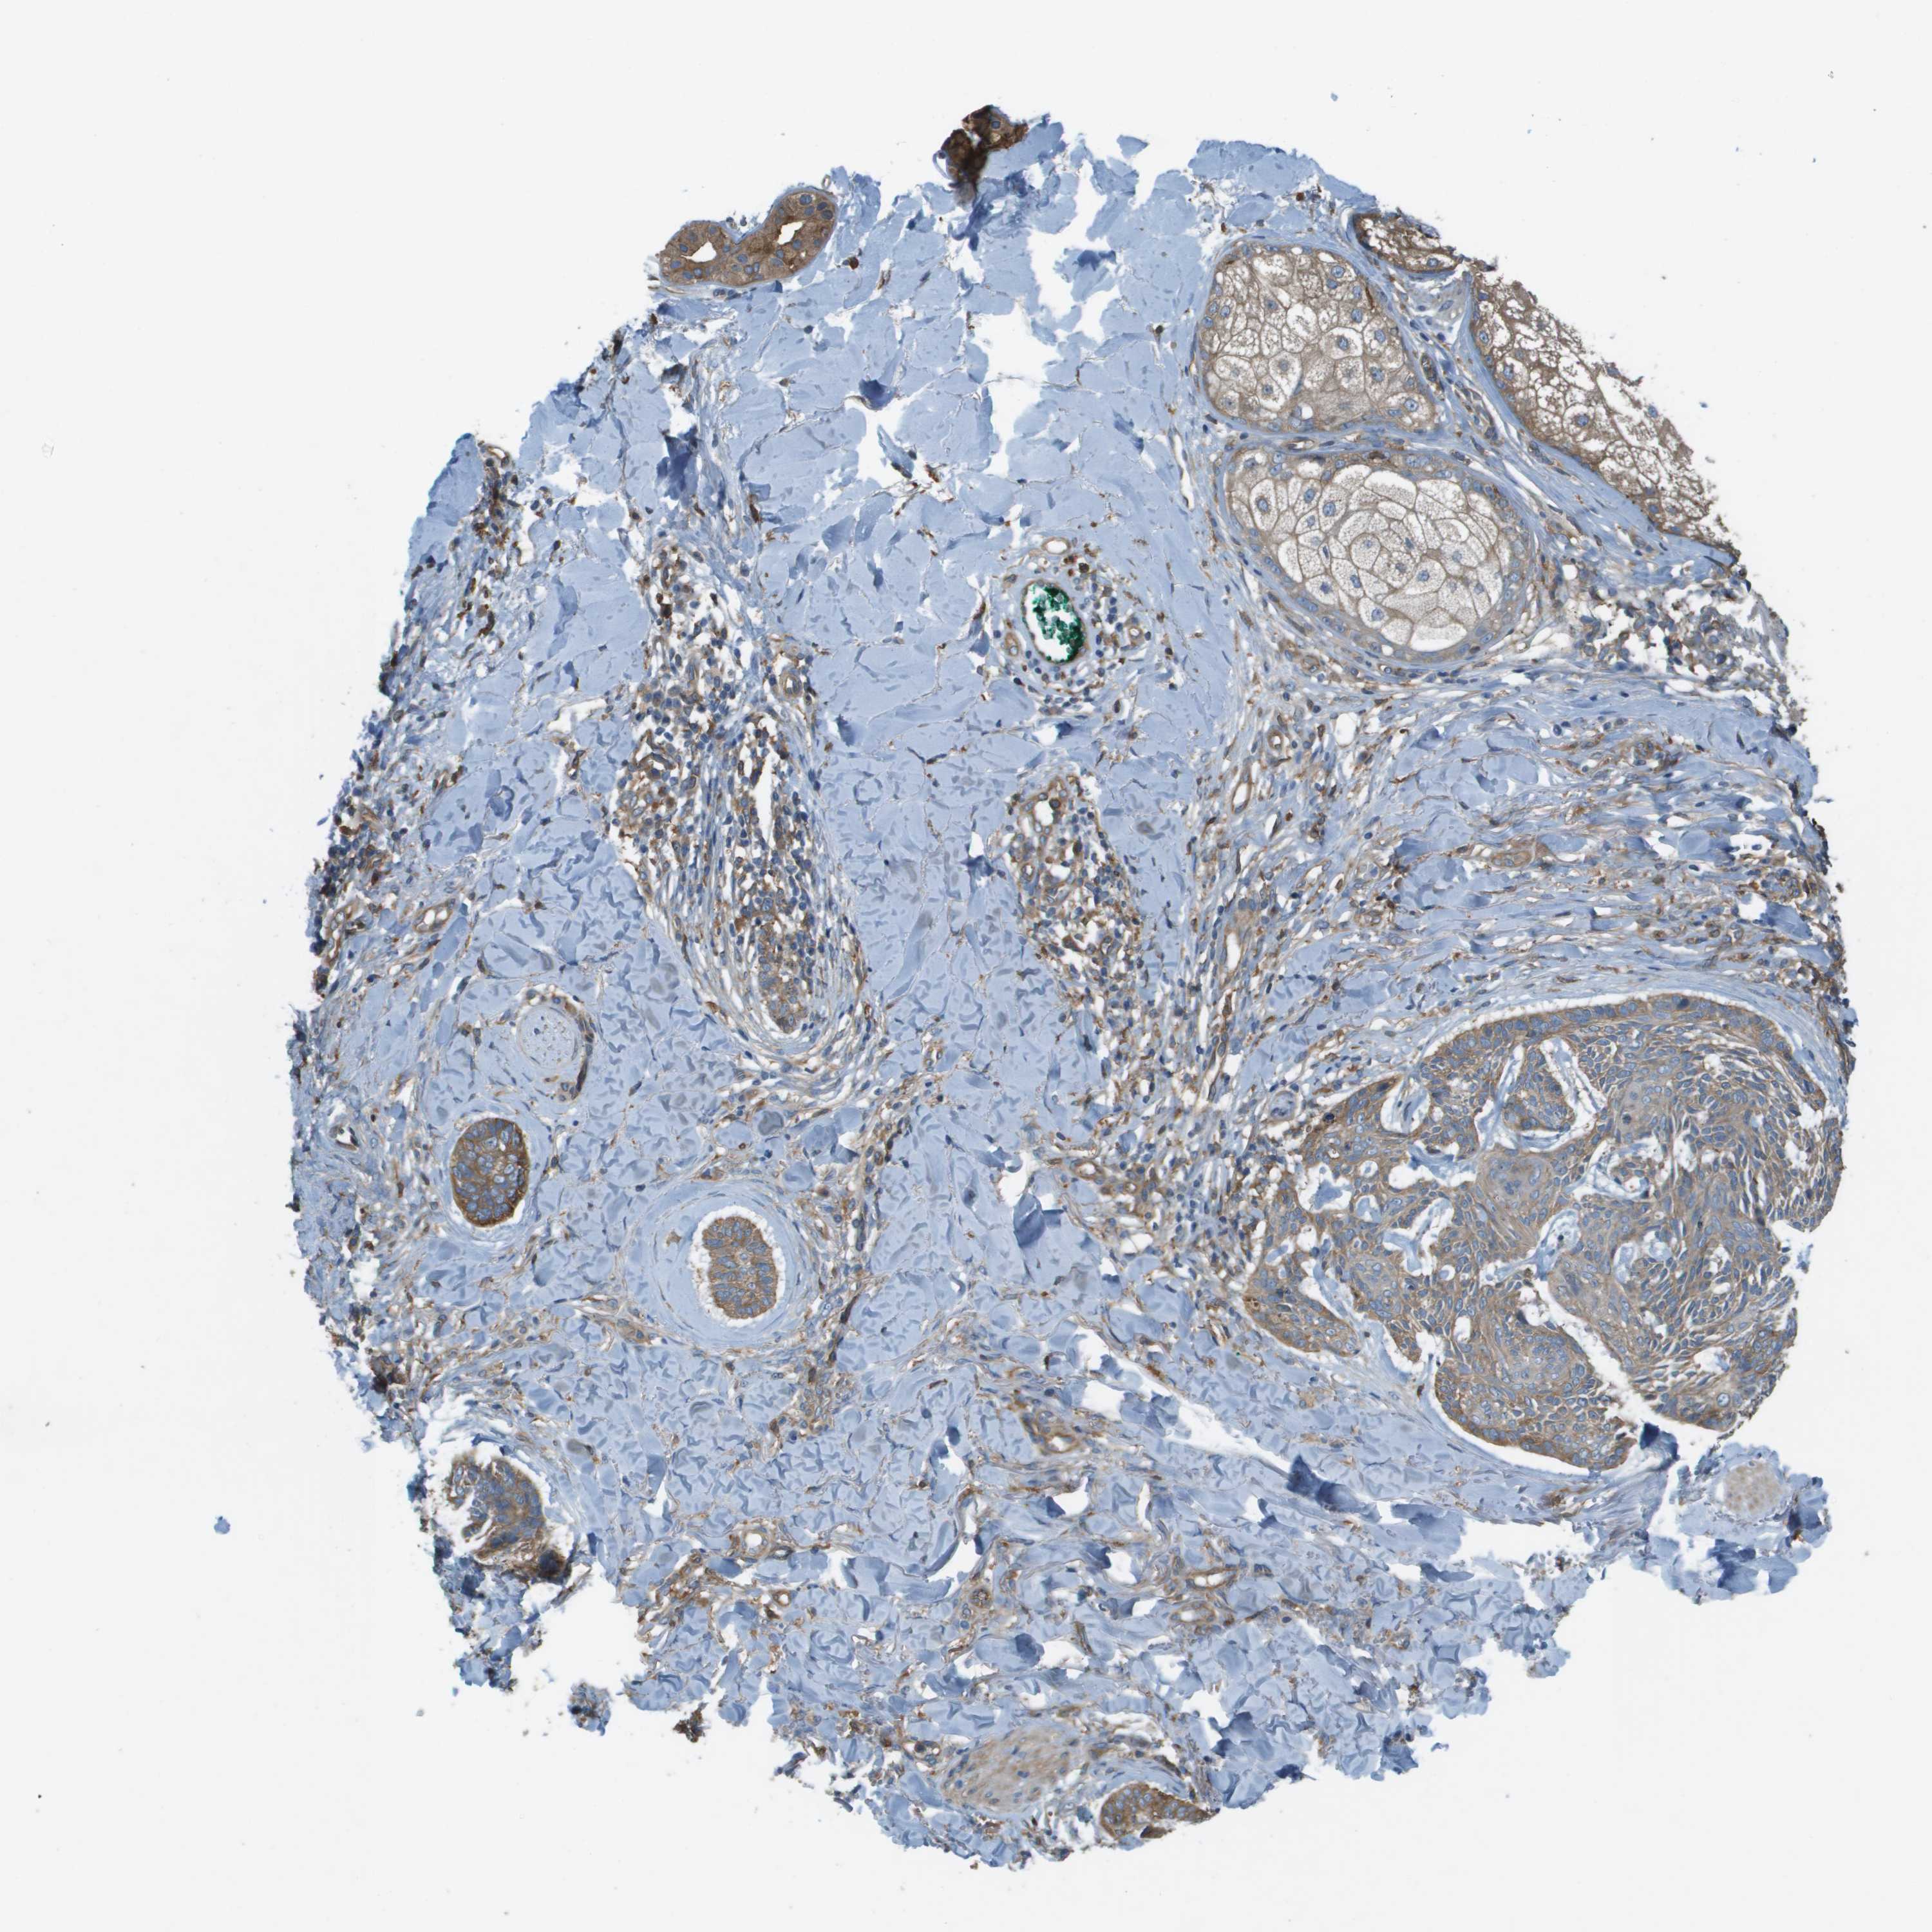

CANCER SKIN CANCER Show tissue menu

SKIN CANCER - Protein expressioni

A mouse-over function shows sample information and annotation data. Click on an image to view it in a full screen mode. Samples can be filtered based on level of antibody staining by selecting one or several of the following categories: high, medium, low and not detected. The assay and annotation is described here.

Each image is clickable and will lead to virtual microscopy that enables deeper exploration of all samples and also displays staining intensity scores, fraction scores and subcellular localization as well as patient and tissue information for each sample.

Antibody CAB017616

Basal cell carcinoma

Squamous cell carcinoma, NOS

Squamous cell carcinoma in situ, NOS

Adnexal tumor, benign